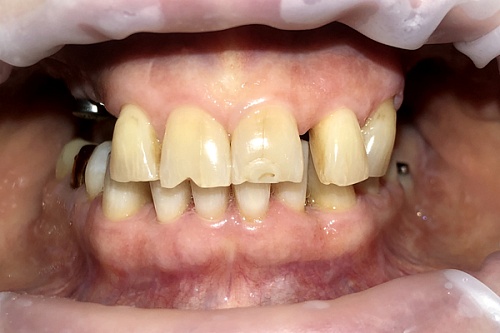

Изменения тканей, которые окружают корни зубов, к сожалению, неизбежны и с возрастом наблюдаются у всех, однако в разном объеме. Так, на развитие пародонтита влияет болезнетворная микрофлора полости рта, которая есть у каждого из нас, но на мы в силах повлиять на ее количество.

Сохранить зубы и пародонт помогает правильная гигиена полости рта дома и в кресле стоматолога, а также своевременное протезирование и имплантация, которые замещают удаленные зубы и равномерно распределяют жевательную нагрузку, не позволяя костной ткани атрофироваться.

Таким образом, по мнению стоматологов, риск возникновения болезней десен на 80% зависит от сознательности самого пациента.